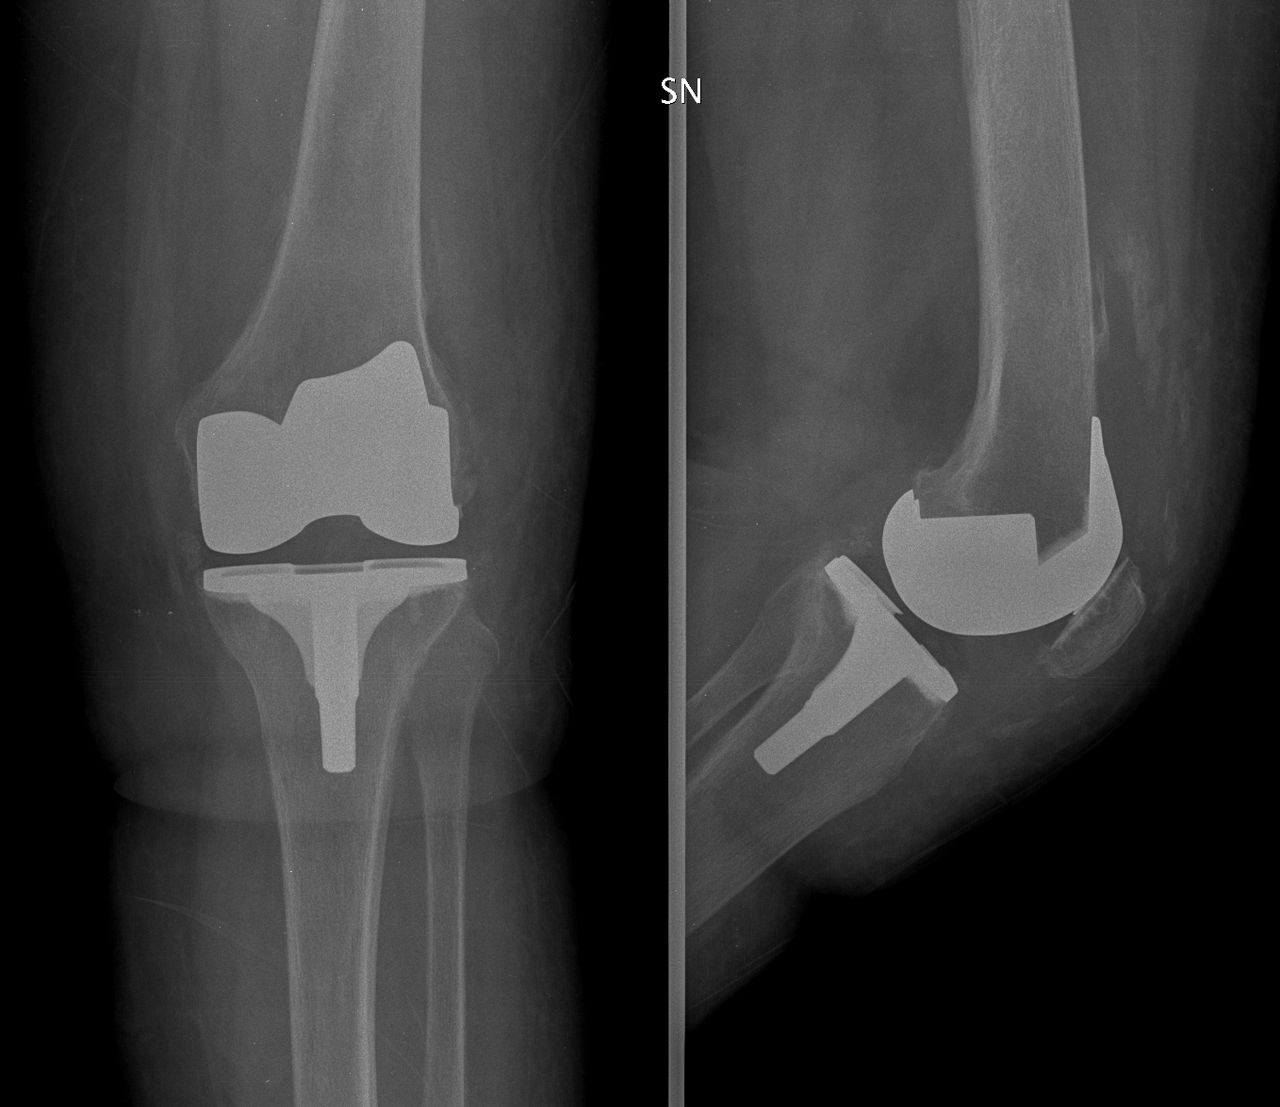

• Chirurgia Protesica Robotica e Tradizionale di Ginocchio e Anca: Interventi chirurgici di sostituzione articolare per il trattamento dell'artrosi.

Negli ultimi anni la chirurgia protesica di ginocchio si è evoluta verso il concetto di allineamento personalizzato. A differenza del tradizionale allineamento meccanico, che porta tutti i pazienti allo stesso asse neutro, l’approccio personalizzato mira a rispettare l’anatomia e la cinematica individuale del ginocchio, riproducendo il più possibile l’assetto naturale pre-artrosico. Questo è reso possibile grazie a sistemi di pianificazione computerizzata e alla chirurgia robotica, che consentono un posizionamento millimetrico delle componenti e un bilanciamento ottimale dei legamenti. L’obiettivo è ridurre le sensazioni di “ginocchio artificiale”, migliorare la funzionalità e garantire un recupero più fisiologico.